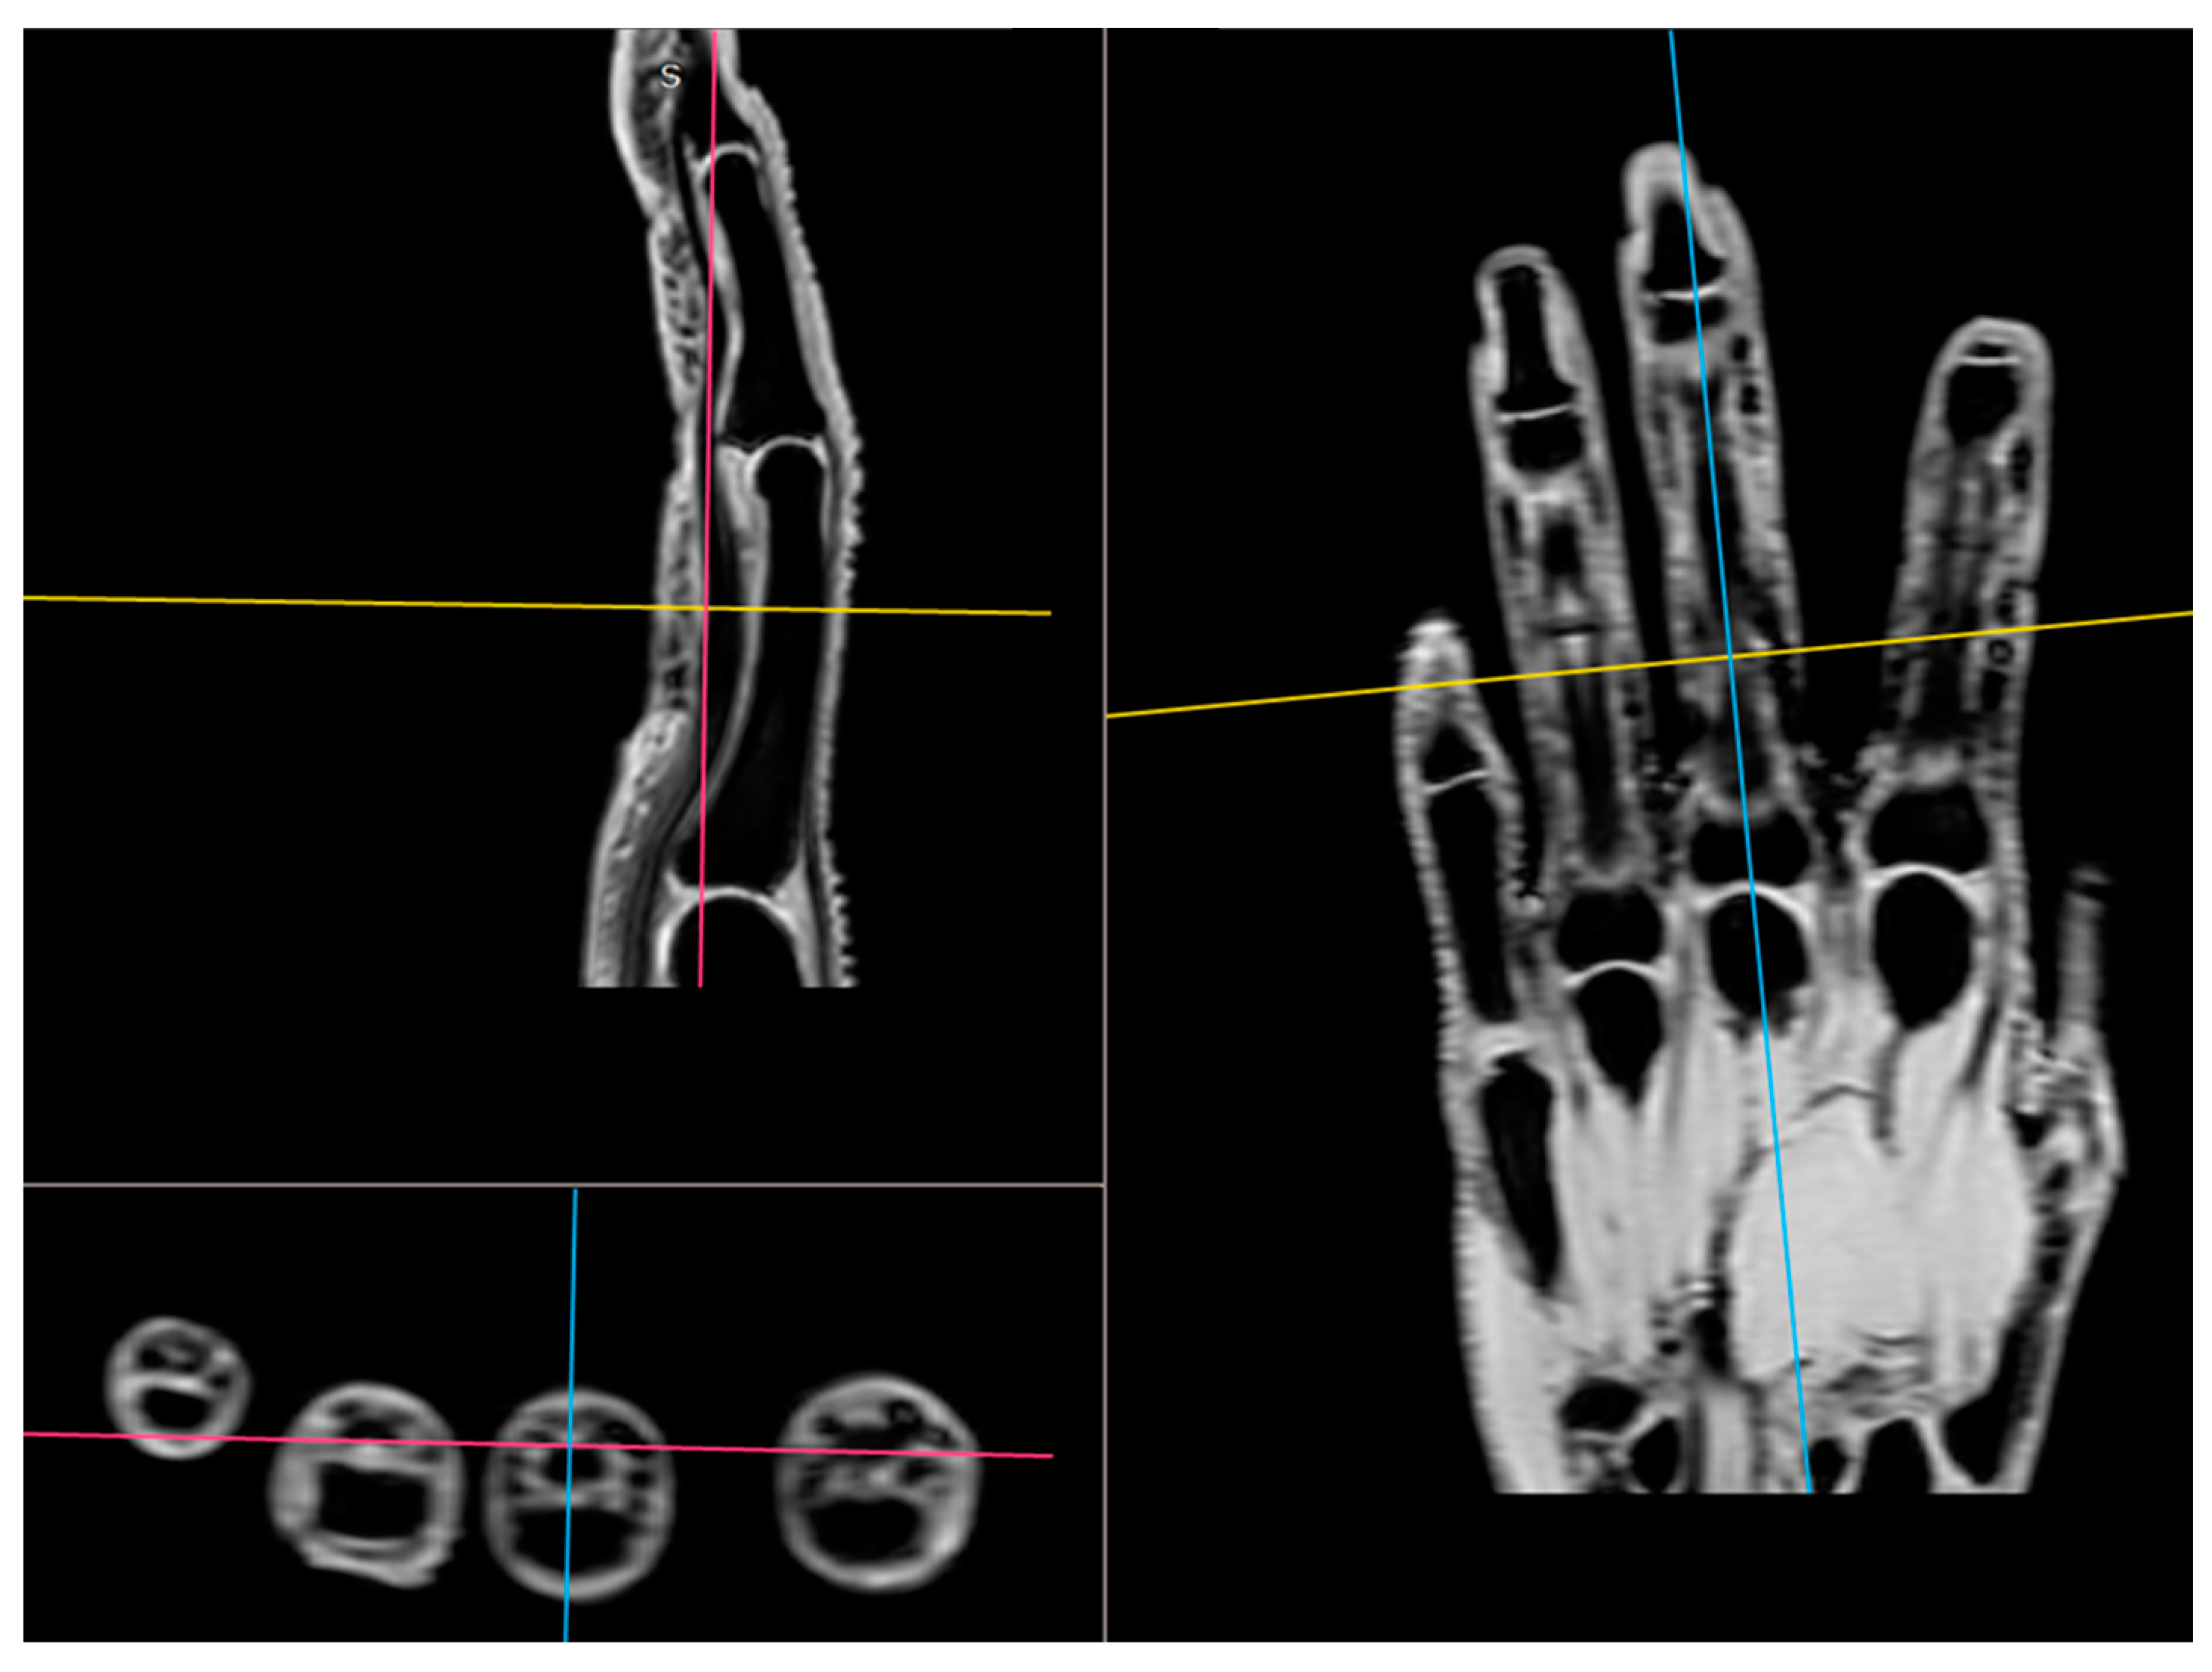

All participants were examined with the three-dimensional quantitative MRI (3D q-MRI). The Philips 3T scanner was used with the coil for small parts. After obtaining structural T1 and T2 scans, the WATS 3D sequence was performed. The WATS sequence is dedicated to the cartilage evaluation and highlights the subchondral cortical layer. Due to the application of a 3D sequence, we were able to obtain the true sagittal cross-section of each finger (Figure 3). This was vital because, in some patients, contractions did not allow for anatomical position of fingers during examination. After adjusting the planes, we measured the distance between two cortical layers for each finger joint in its middle transverse dimension, obtaining three measurements (in volar 1/3, dorsal 1/3, and middle 1/3) and calculating a mean (Figure 4 and Figure 5). The distal phalanx length (DPL), the cartilage thickness of distal interphalangeal joints (DIPJ), proximal interphalangeal joints (PIPJ), interphalangeal joint (IPJ), and metacarpophalangeal joints (MCPJ) in all participants were measured.

Figure 3.

The application of a 3D sequence of MRI to obtain the true sagittal cross-section of each finger.